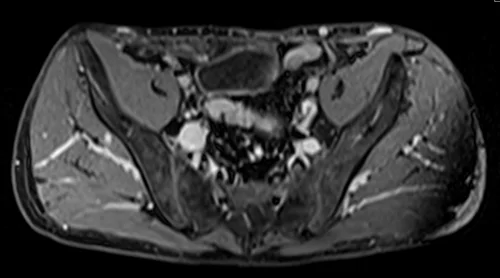

MRV abdomen axial t1 flash post contrast image 1 - MRI